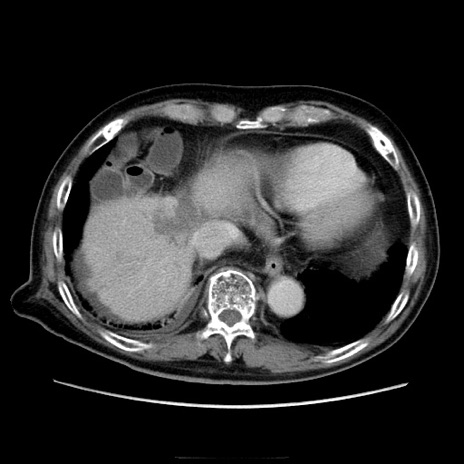

症例21(横断像)

【症例】70歳代男性

【主訴】腹痛

【現病歴】肝硬変・肝細胞癌にてかかりつけの方。約9時間前に食後より腹痛出現。症状が徐々に増悪し、嘔吐出現したため来院。

【既往歴】肝硬変、肝細胞癌(RFA、TACE後)

【身体所見】意識清明、表情苦悶様、BT 36℃、BP 129/78mmHg、P 88bpm、SpO2 97%(RA)、右上腹部から心窩部にかけて圧痛あり、反跳痛なし、筋性防御あり。

【データ】WBC 5800、CRP 0.16